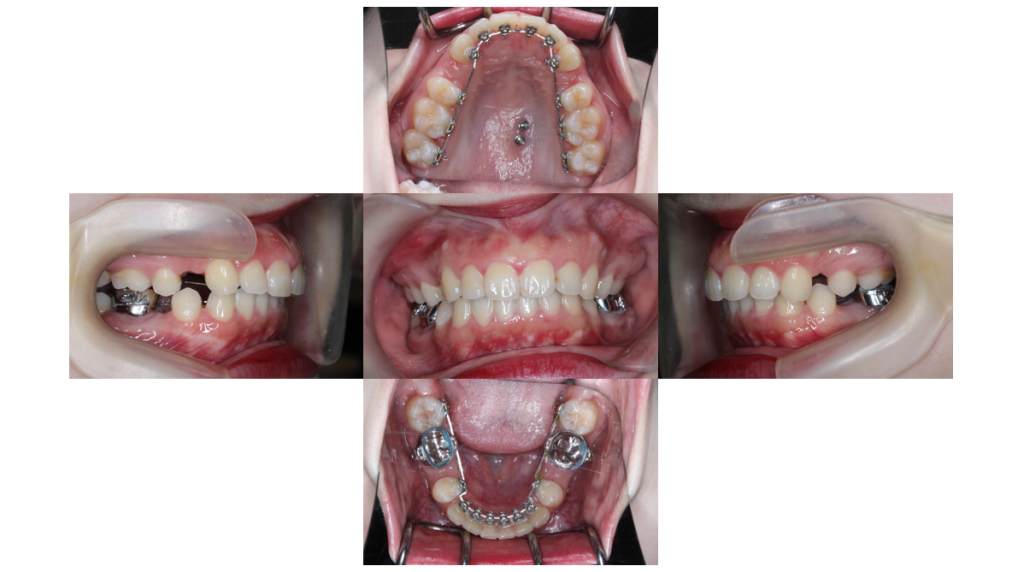

約12ヶ月経過

上顎前突・裏側矯正の症例下顎から抜歯したスペースを閉じていきます